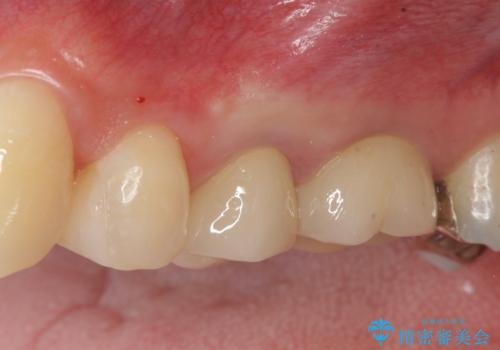

老朽化した前歯のセラミック治療やりかえ

- 20年前に治療した前歯のセラミッククラウンが老朽化し見た目の改善を求めて来院されました。

不十分な根管治療を含めたセラミッククラウンのやりかえ治療を計画します。

クラウン治療は経年的に歯ぐきの位置が変わり汚れが溜まってしまったり、見た目が悪くなるなどの問題が出てくることがあります。

現在の歯ぐきの位置できっちりと仕上げることで見た目の改善が達成されました。